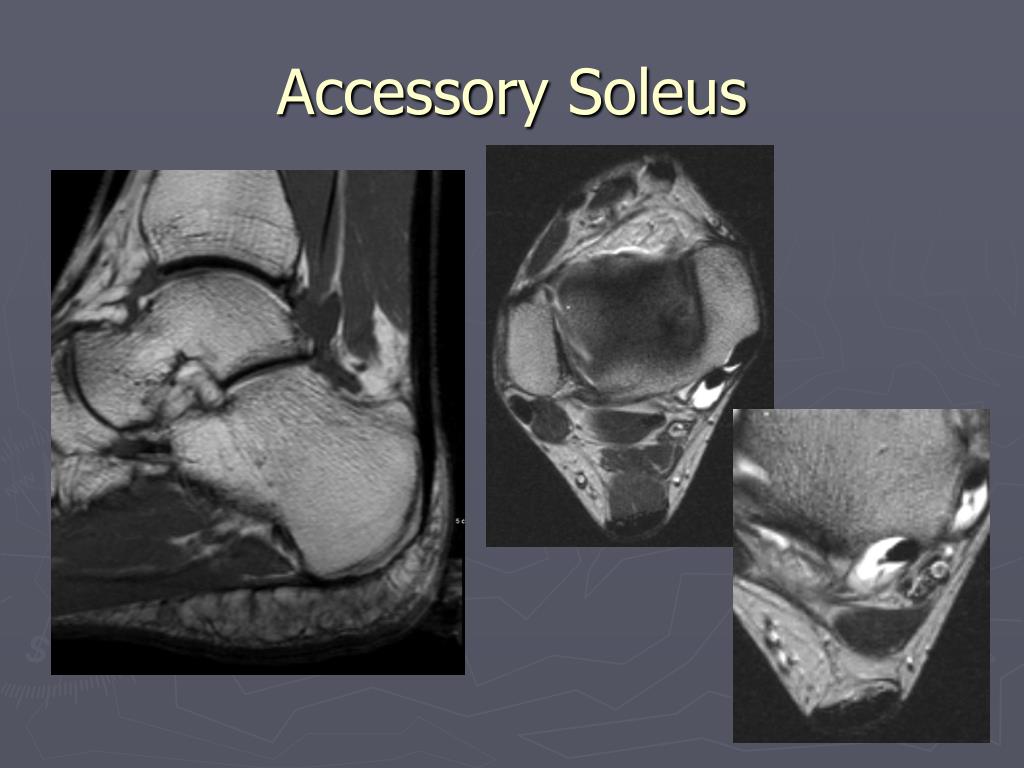

PPT Musculoskeletal MRI PowerPoint Presentation, free download ID Accessory Soleus Xray There are multiple cases of symptomatic pain associated with the accessory soleus muscle, most of them are asymptomatic. Accessory soleus muscle (asm) is a rare supernumerary anatomical variant that. The accessory soleus (as) is a relatively uncommon developmental variant, with reported prevalence ranging from 0.7% to 11.6% in the. Accessory soleus muscle (asm) is a rare congenital variation that presents. Accessory Soleus Xray.